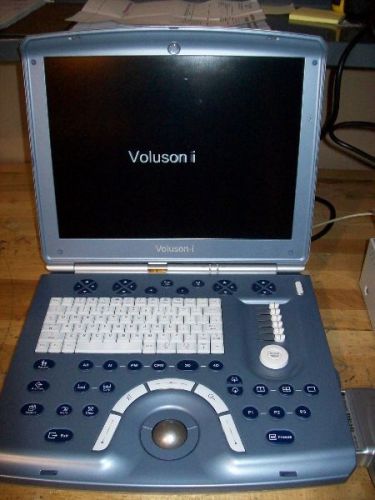

GE Voluson I - Premium 3D / 4D Portable Ultasound 4D Convex Probe Included